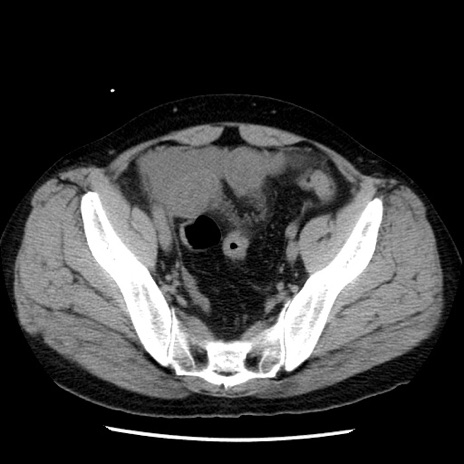

冠状断像

【症例】40歳代男性

【現病歴】2日前から胃痛あり。徐々に周期的な激痛に変化した。本日になっても激痛があるため受診。

【身体所見】意識清明、BT 38-39℃台あり、腹部:膨満、やや硬、右下腹部に圧痛あり。

【データ】WBC 8500、CRP 23.26